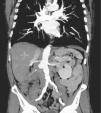

Aneurisma micótico de la aorta abdominal tras tratamiento intravesical con bacilo de Calmette-Guèrin

Mycotic abdominal aortic aneurysm following intravesical Bacillus Calmette-Guerin therapy